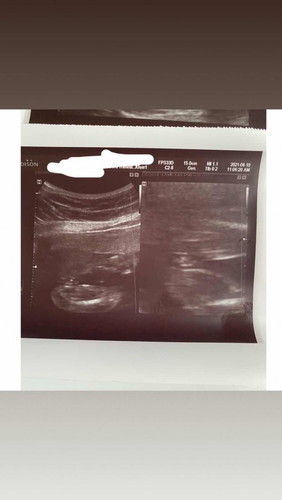

Girl or Boy?

What do you think mommies? π₯°π₯°π₯° Hamburger ba or turtle? Hehehehe

turtle hahahah, pututoy nakikita koπππππππππππ